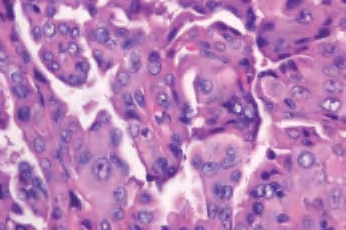

3.镜下 为复杂分支状乳头,含纤维血管轴心,细胞拥挤,核增大,呈卵圆形、沙砾体,表面被以单层柱状上皮,半数以上核呈毛玻璃样,有核沟,核内假包涵体(图3-40至图3-43)。

图3-42 甲状腺乳头状癌,箭头处核内假包涵体

图3-43 甲状腺乳头状癌,毛玻璃样核,箭头处为核沟